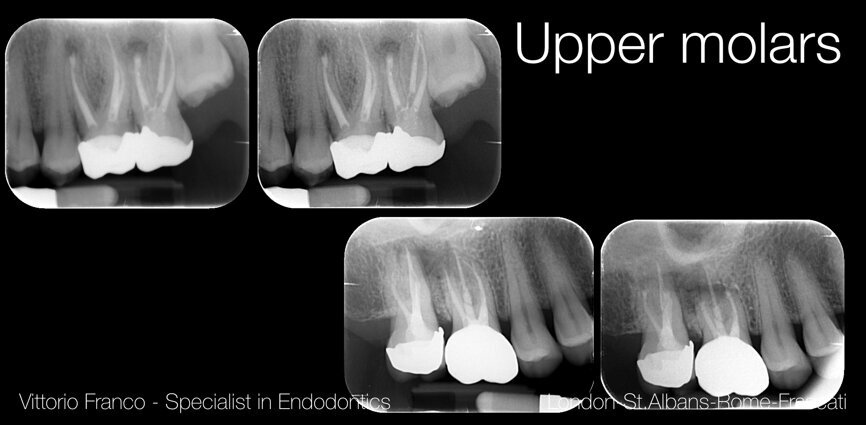

„Endodoncja IV” wg dr. Vittorio Franco: zarządzanie trudnymi przypadkami

Centrum Kursowe Dentist zaprasza na 1-dniowy kurs praktyczny z dr. Vittorio Franco – „Resekcja wierzchołka i wsteczne wypełnianie kanału – zarządzenie trudnymi przypadkami”, który odbędzie się 5 października br. w Krakowie. Kurs prowadzony będzie w języku angielskim z tłumaczeniem na język polski.

Mikroresekcja wierzchołka korzenia może być obecnie wykonana w przewidywalny sposób. Ważna jest odpowiednia kwalifikacja przypadku do zabiegu, umiejętność wykonania właściwego płata, dojścia do wierzchołka korzenia, a także technika wstecznego wypełnienia kanału korzenia. Te wszystkie czynniki zadecydują o końcowym sukcesie leczenia. Aby jednak leczyć przewidywalnie, warto przećwiczyć krok po kroku tą technikę na kursie praktycznym. Taka możliwość pojawi się podczas kursu dr. Vittorio Franco – światowego autorytetu w dziedzinie trudnych przypadków endodontycznych.